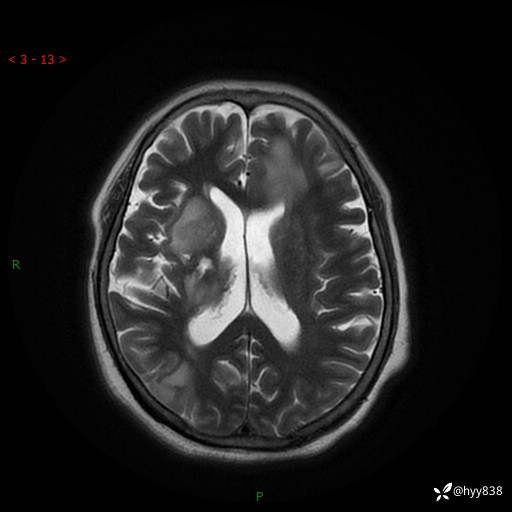

颅脑MRI(T2WI+DWI)